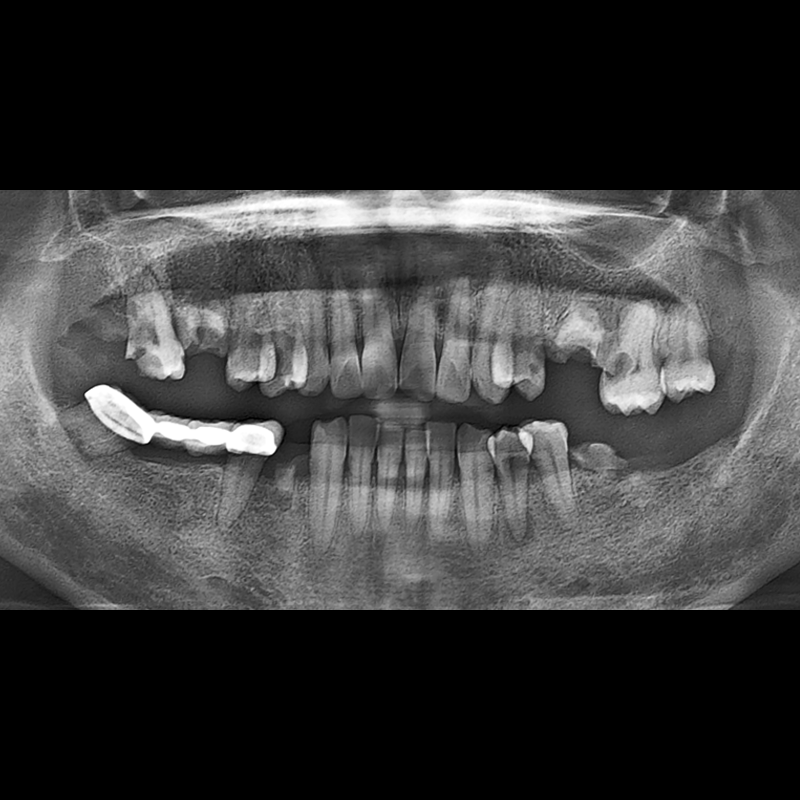

BEFORE AFTER

インプラント手術事例 2025.12.10

欠損した歯の部分と、生かしにくい歯の位置にインプラントを植立しました。